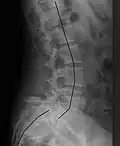

| X-ray of the lateral lumbar spine with a grade III anterolisthesis at the L5-S1 level | |

Spondylolisthesis refers to a condition in which one spinal vertebra slips out of place compared to another.[1] While some medical dictionaries define spondylolisthesis specifically as the forward or anterior displacement of a vertebra over the vertebra inferior to it (or the sacrum),[2][3] it is often defined in medical textbooks as displacement in any direction.[4][5]

Spondylolisthesis is graded based upon the degree of slippage of one vertebral body relative to the subsequent adjacent vertebral body.[6] Spondylolisthesis is classified as one of the six major etiologies: degenerative, traumatic, dysplastic, isthmic, pathologic, or post-surgical.[7] Spondylolisthesis most commonly occurs in the lumbar spine, primarily at the L5-S1 level, with the L5 vertebral body anteriorly translating over the S1 vertebral body.[7]

Classification by degree of the slippage, as measured as percentage of the width of the vertebral body:[17] Grade I spondylolisthesis accounts for approximately 75% of all cases.[7]

- Grade I: 0–25%

- Grade II: 25–50%

- Grade III: 50–75%

- Grade IV: 75–100%

- Grade V: greater than 100%

Plain radiography (X-ray)

Plain radiography is often the first step in medical imaging.[22] Anteroposterior (front-back) and lateral (side) images are used to allow the physician to view the spine at multiple angles.[22] Oblique view are no longer recommended.[33][34] In evaluating for spondylolithesis, plain radiographs provide information on the positioning and structural integrity of the spine. Therefore, if further detail is needed, a physician may request advanced imaging.